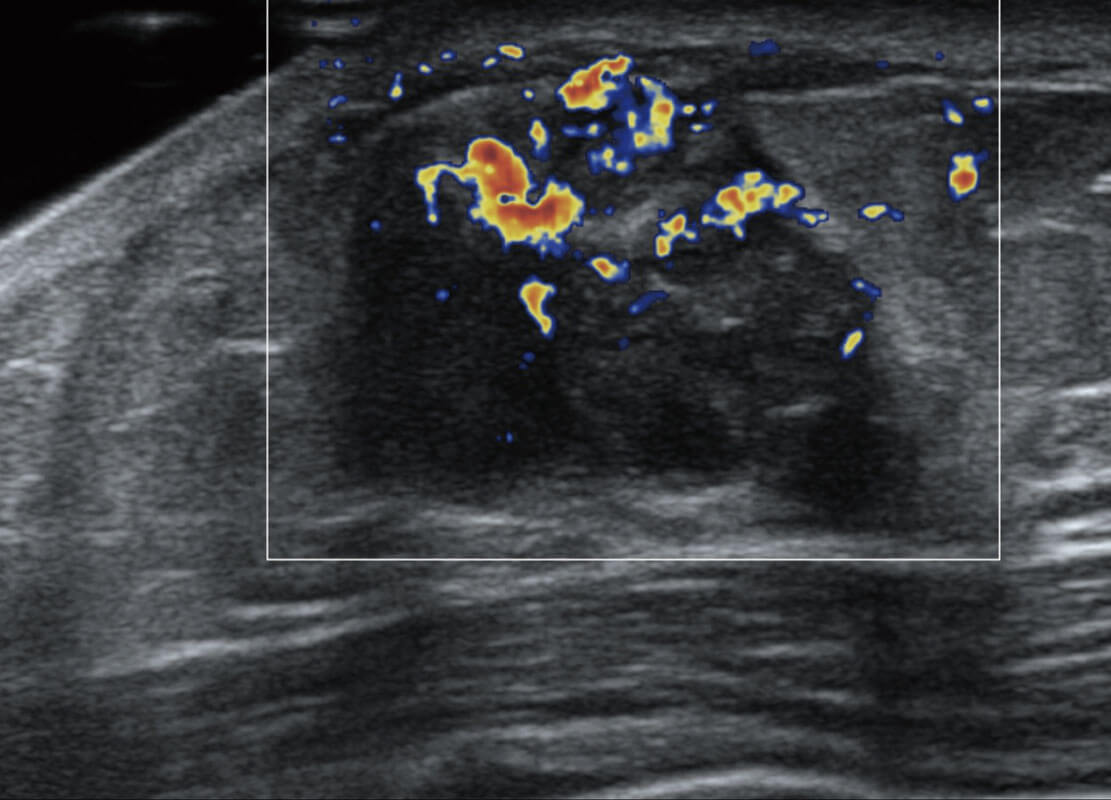

P60优异的图像质量搭载专科探头,在妇科基础疾病的诊断、卵泡生长的监测、输卵管通畅情况的判别等方面为您提供生殖应用方案。

腔内妇科-宫腔分离

腔内妇科-卵巢